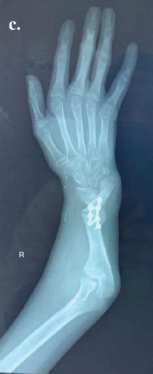

Ballistic Galeazzi Fractures: A Case Series

Timothy Westbrooks , Haley Tornberg , Kevin Heo , Olivia Jagiella-Lodise , Nicole Zelenski